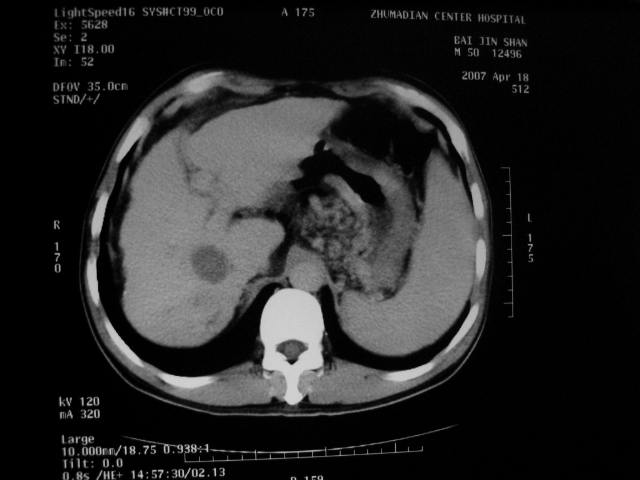

动脉期病灶见轻度强化,考虑肝癌可能性大。

考虑肝硬化,右肝癌可能性大。

1、肝右叶低密度灶考虑肝癌

2、肝硬化

肝硬化、脾大,静脉曲张,肝右叶低密度灶,增强无明显强化,还是考虑肝癌可能性大,建议结合afp检查。

考虑肝硬化,脾大,静脉曲张,肝右叶低密度灶,右肝癌可能性大。